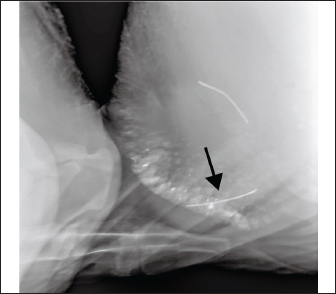

X-ray examination revealed a metallic foreign body in the reticulum (Fig. 2). The rumen fluid pH was approximately 8.5. Based on the above results, the cow was diagnosed with TR and AI. Based on previous reports (Braun et al., 2020), the diagnosis of TR can be confirmed by foreign body tests and X-ray examination. However, the differential diagnoses include forestomach atony (FA), rumen obstruction (RO), omasal obstruction (OO), left displaced abomasum (LDA), abomasal torsion (AT), and intestinal obstruction (IO) (Table 1).

Fig. 2. X-ray showing a metal foreign body inserted into the fundus of the reticulum.